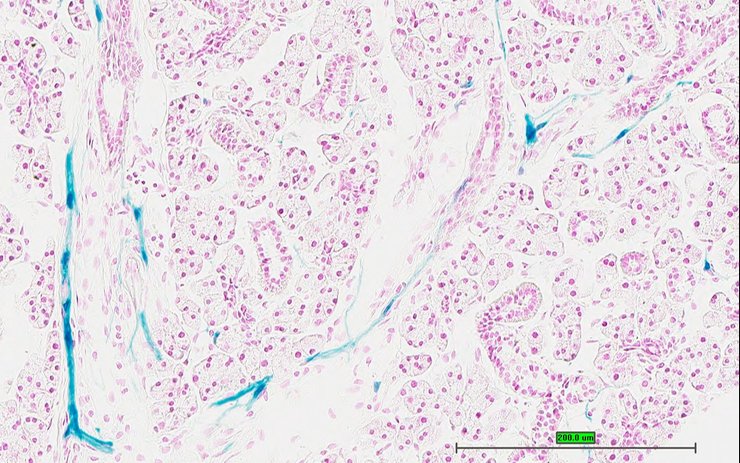

TS28: pancreas Present UC Davis_1876100

Specimen UC Davis_1876101: postnatal adult; Kcna1tm1.1(KOMP)Vlcg/Kcna1+ (more )

TS28: pancreas Present UC Davis_1876031

Specimen UC Davis_1876032: postnatal adult; Kcna1tm1.1(KOMP)Vlcg/Kcna1+ (more )

Structure Level Pattern Image Note

TS28: pancreas Present UC Davis_1876032

Specimen UC Davis_1876033: postnatal adult; Kcna1tm1.1(KOMP)Vlcg/Kcna1+ (more )

TS28: pancreas Present UC Davis_1876033

Specimen UC Davis_1876034: postnatal adult; Kcna1tm1.1(KOMP)Vlcg/Kcna1+ (more )

TS28: pancreas Present UC Davis_1876034